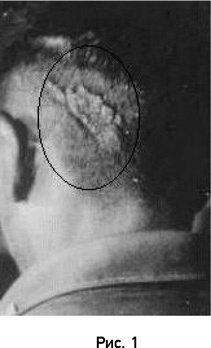

Большой бородавчатый эпидермальный невус на голове таитянского юноши, который, будучи ребенком, имел воспоминания о жизни своего дяди по отцу, убитого ударом в голову тяжелым ножом.

Фактор случайного совпадения родимых пятен и ран значительно уменьшается, когда ребенок имеет два или больше родимых пятна, соответствующих ранам на теле погибшего человека, о жизни которого он помнит. Показанное на рисунке 1 необычное изменение кожного покрова в затылочной части головы таитянского юноши соответствует его описанию смерти дяди, наступившей почти мгновенно от удара ножа. Мальчик также имел врожденную деформацию ногтя на большом пальце ноги, что соответствует наличию у дяди хронического воспалительного процесса инфекционного происхождения на том же пальце ноги, которым он страдал в течение нескольких лет до смерти.